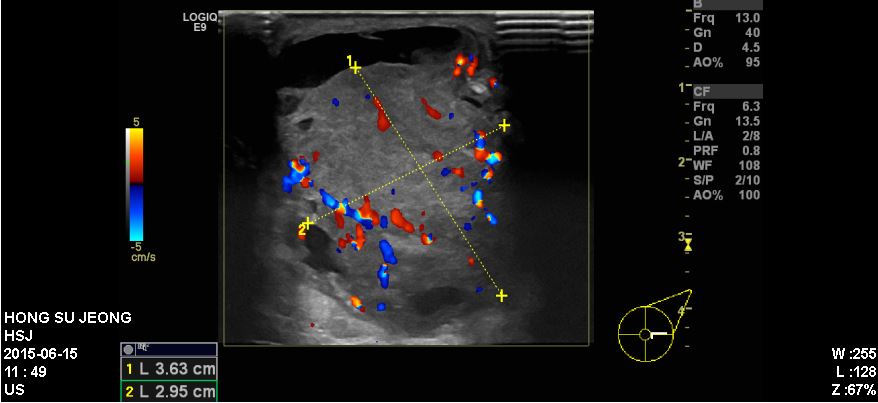

좌측유방에 만져지는 혹으로 내원하신 40대 환자분이십니다.

본원에서 시행한 유방초음파상에 확인되는 좌측 3시방향에 혹을 조직검사시행하였고

결과상 침윤성유관암 진단되었습니다.